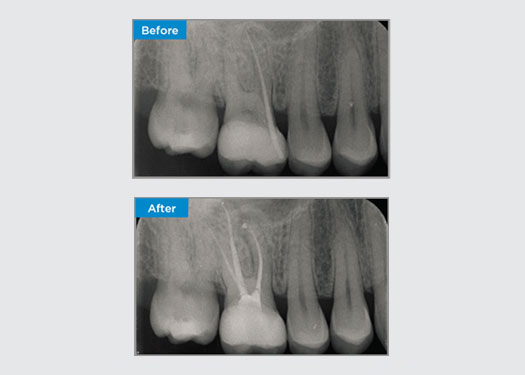

Il paziente presentava parodontite apicale asintomatica al dente 34. Dalla radiografia preoperatoria, il dente 34 presentava due radici visibili. Tuttavia, una scansione CBCT ha confermato un premolare a tre radici e i canali si sono divisi in tre alla radice centrale. Un’attenta selezione dello strumento è fondamentale per questo dente delicato.

Dott. Jack Lin, Endodontista, Sidney, NSW Australia

In questa situazione, la conservazione della struttura dente/radice è essenziale per ridurre il rischio di cedimento, trasporto, zip, perforazione e frattura della radice. La selezione dei casi, la diagnosi e la pianificazione pre-trattamento sono importanti. La selezione degli strumenti endodontici con flessibilità, efficienza e rispetto dell’anatomia naturale della radice è fondamentale.